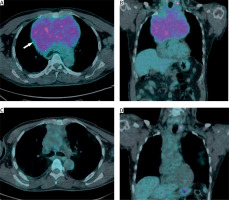

PET CT is recommended when malignant and benign discrimination is required in mediastinal tumors. In the Tatci et al. study, the sensitivity of PET CT was 90% and the specificity was 55.17%. To distinguish malignant and benign lesions, the cut-off value of SUVmax was reported to be 4.67 [18]. The highest SUVmax value of our patients’ PET-CT results was 20.1, and the mean SUVmax value was 11.6. We present PET-CT images before and after chemotherapy in our patient with primary mediastinal seminoma in Figure 2. He received 6 cycles of bleomycin, etoposide and cisplatin chemotherapy and then we found that there was a complete response in the mass with control PET CT (Figure 2).

Figure 2

A, B – Axial and coronal sections of the PET CT showing high FDG uptake in the thyroid tissue and mediastinal mass (arrow). C, D – After chemotherapy PET-CT scan showing the full response in the mediastinal mass